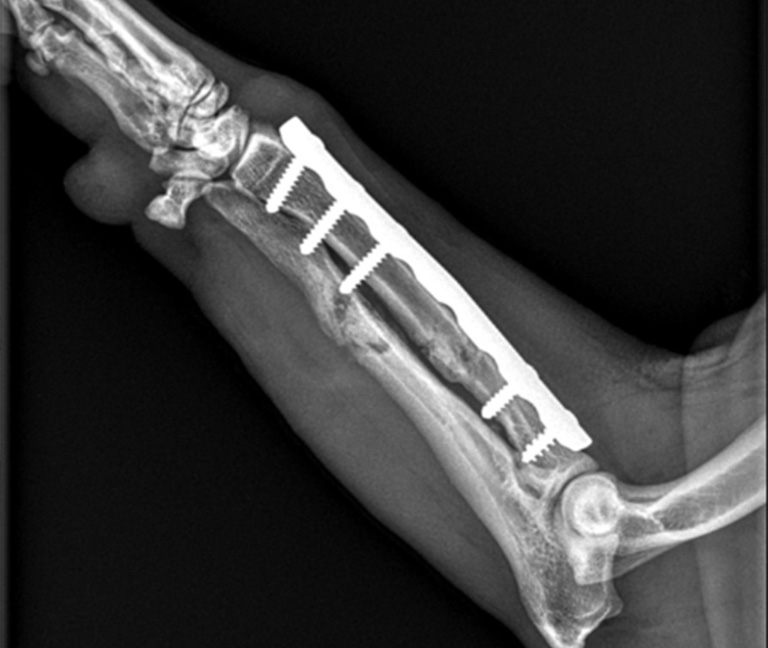

Chirurgie orthopédique

Prise en charge des affections articulaires et osseuses, en collaboration avec Vetmidi Etoy.